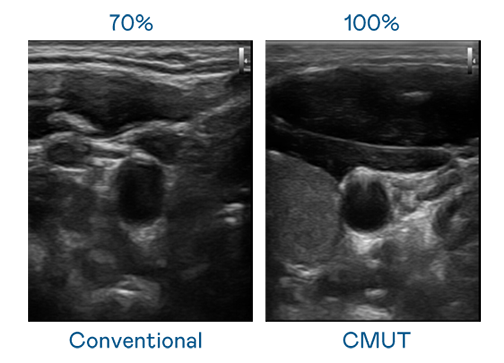

CMUT 技術是一種用電容式微機電元件來產生超音波訊號的技術。與傳統 PZT 壓電式技術相比,CMUT 頻寬增加 30%,更寬頻的超音波訊號讓影像解析度大幅提升,是實現高影像品質醫療超音波掃描、促進精準醫療發展的關鍵技術。

超音波影像的解析度高低,首先取決於探頭能發出的訊號頻寬。乐天使 CMUT 可提供高清晰的超音波訊號,提供高頻寬、高靈敏度、影像紋理細節更高的超音波影像,協助醫護人員縮短影像判讀時間及利用精準的醫療影像進行診斷。